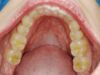

Mann kann hier sehr gut an den beiden Punkten der distalen Dreipunktabstützung erkennen, mit welch hoher Passgenauigkeit die Zentrikplatten auf die Gipszähne der Meistermodelle aufgebacht werden können und müssen.

Es ist einer dieser Detailpunkte, der darüber entscheidet, mit welcher Anfangspassgenauigkeit ein 'A'ufbissbehelf am Ende eines langwierigen Arbeitsprozesses in der Mundhöhle des Patienten eingeglidert werden kann.